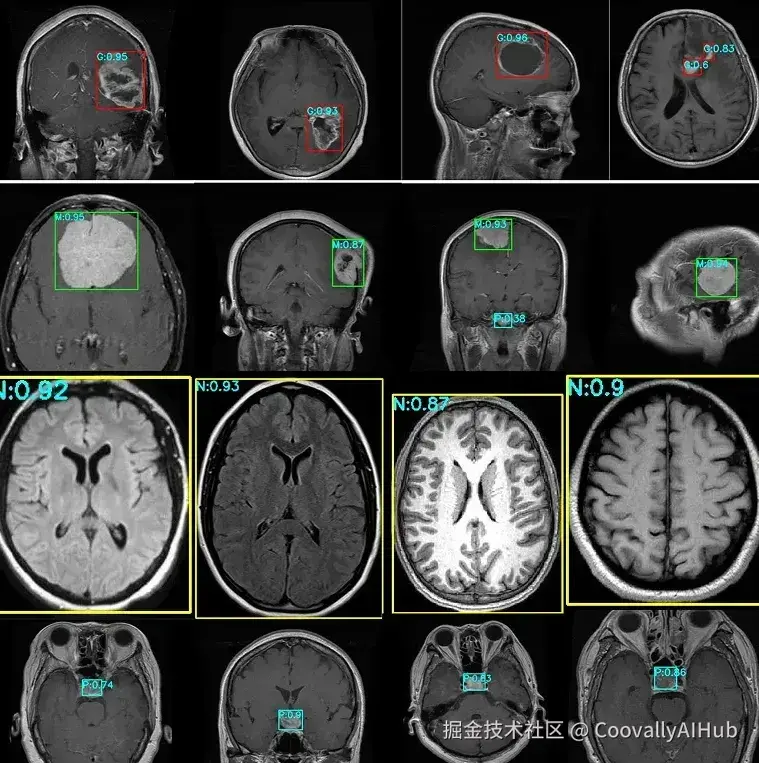

- 医疗保健领域的视觉辅助诊断

医生们常常花费大量时间查看医学影像,以确保不会遗漏任何信息。如今,许多医院开始探索尖端的目标检测技术来帮助加快这一过程。这反映了医疗保健领域的一个更广泛趋势:视觉AI正越来越多地用于支持早期检测、快速诊断和更一致的影像分析。

目标检测可用于快速突显可能需要关注的区域,从而辅助决策并改善患者治疗效果。例如,像YOLO11这样的模型可以帮助医生在MRI扫描中发现脑肿瘤。

由于YOLO11能够识别MRI扫描中的细微模式,它可以帮助更准确地发现小型或早期肿瘤。虽然医生做出最终诊断,但像YOLO11这样的工具可以通过更早地提示潜在问题来帮助简化他们的审阅工作,确保重要的信息不被遗漏。